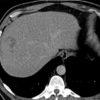

Sán lá gan

» Thông tin: Nam giới – 52 tuổi.

» Lâm sàng: Kiểm tra sức khỏe.